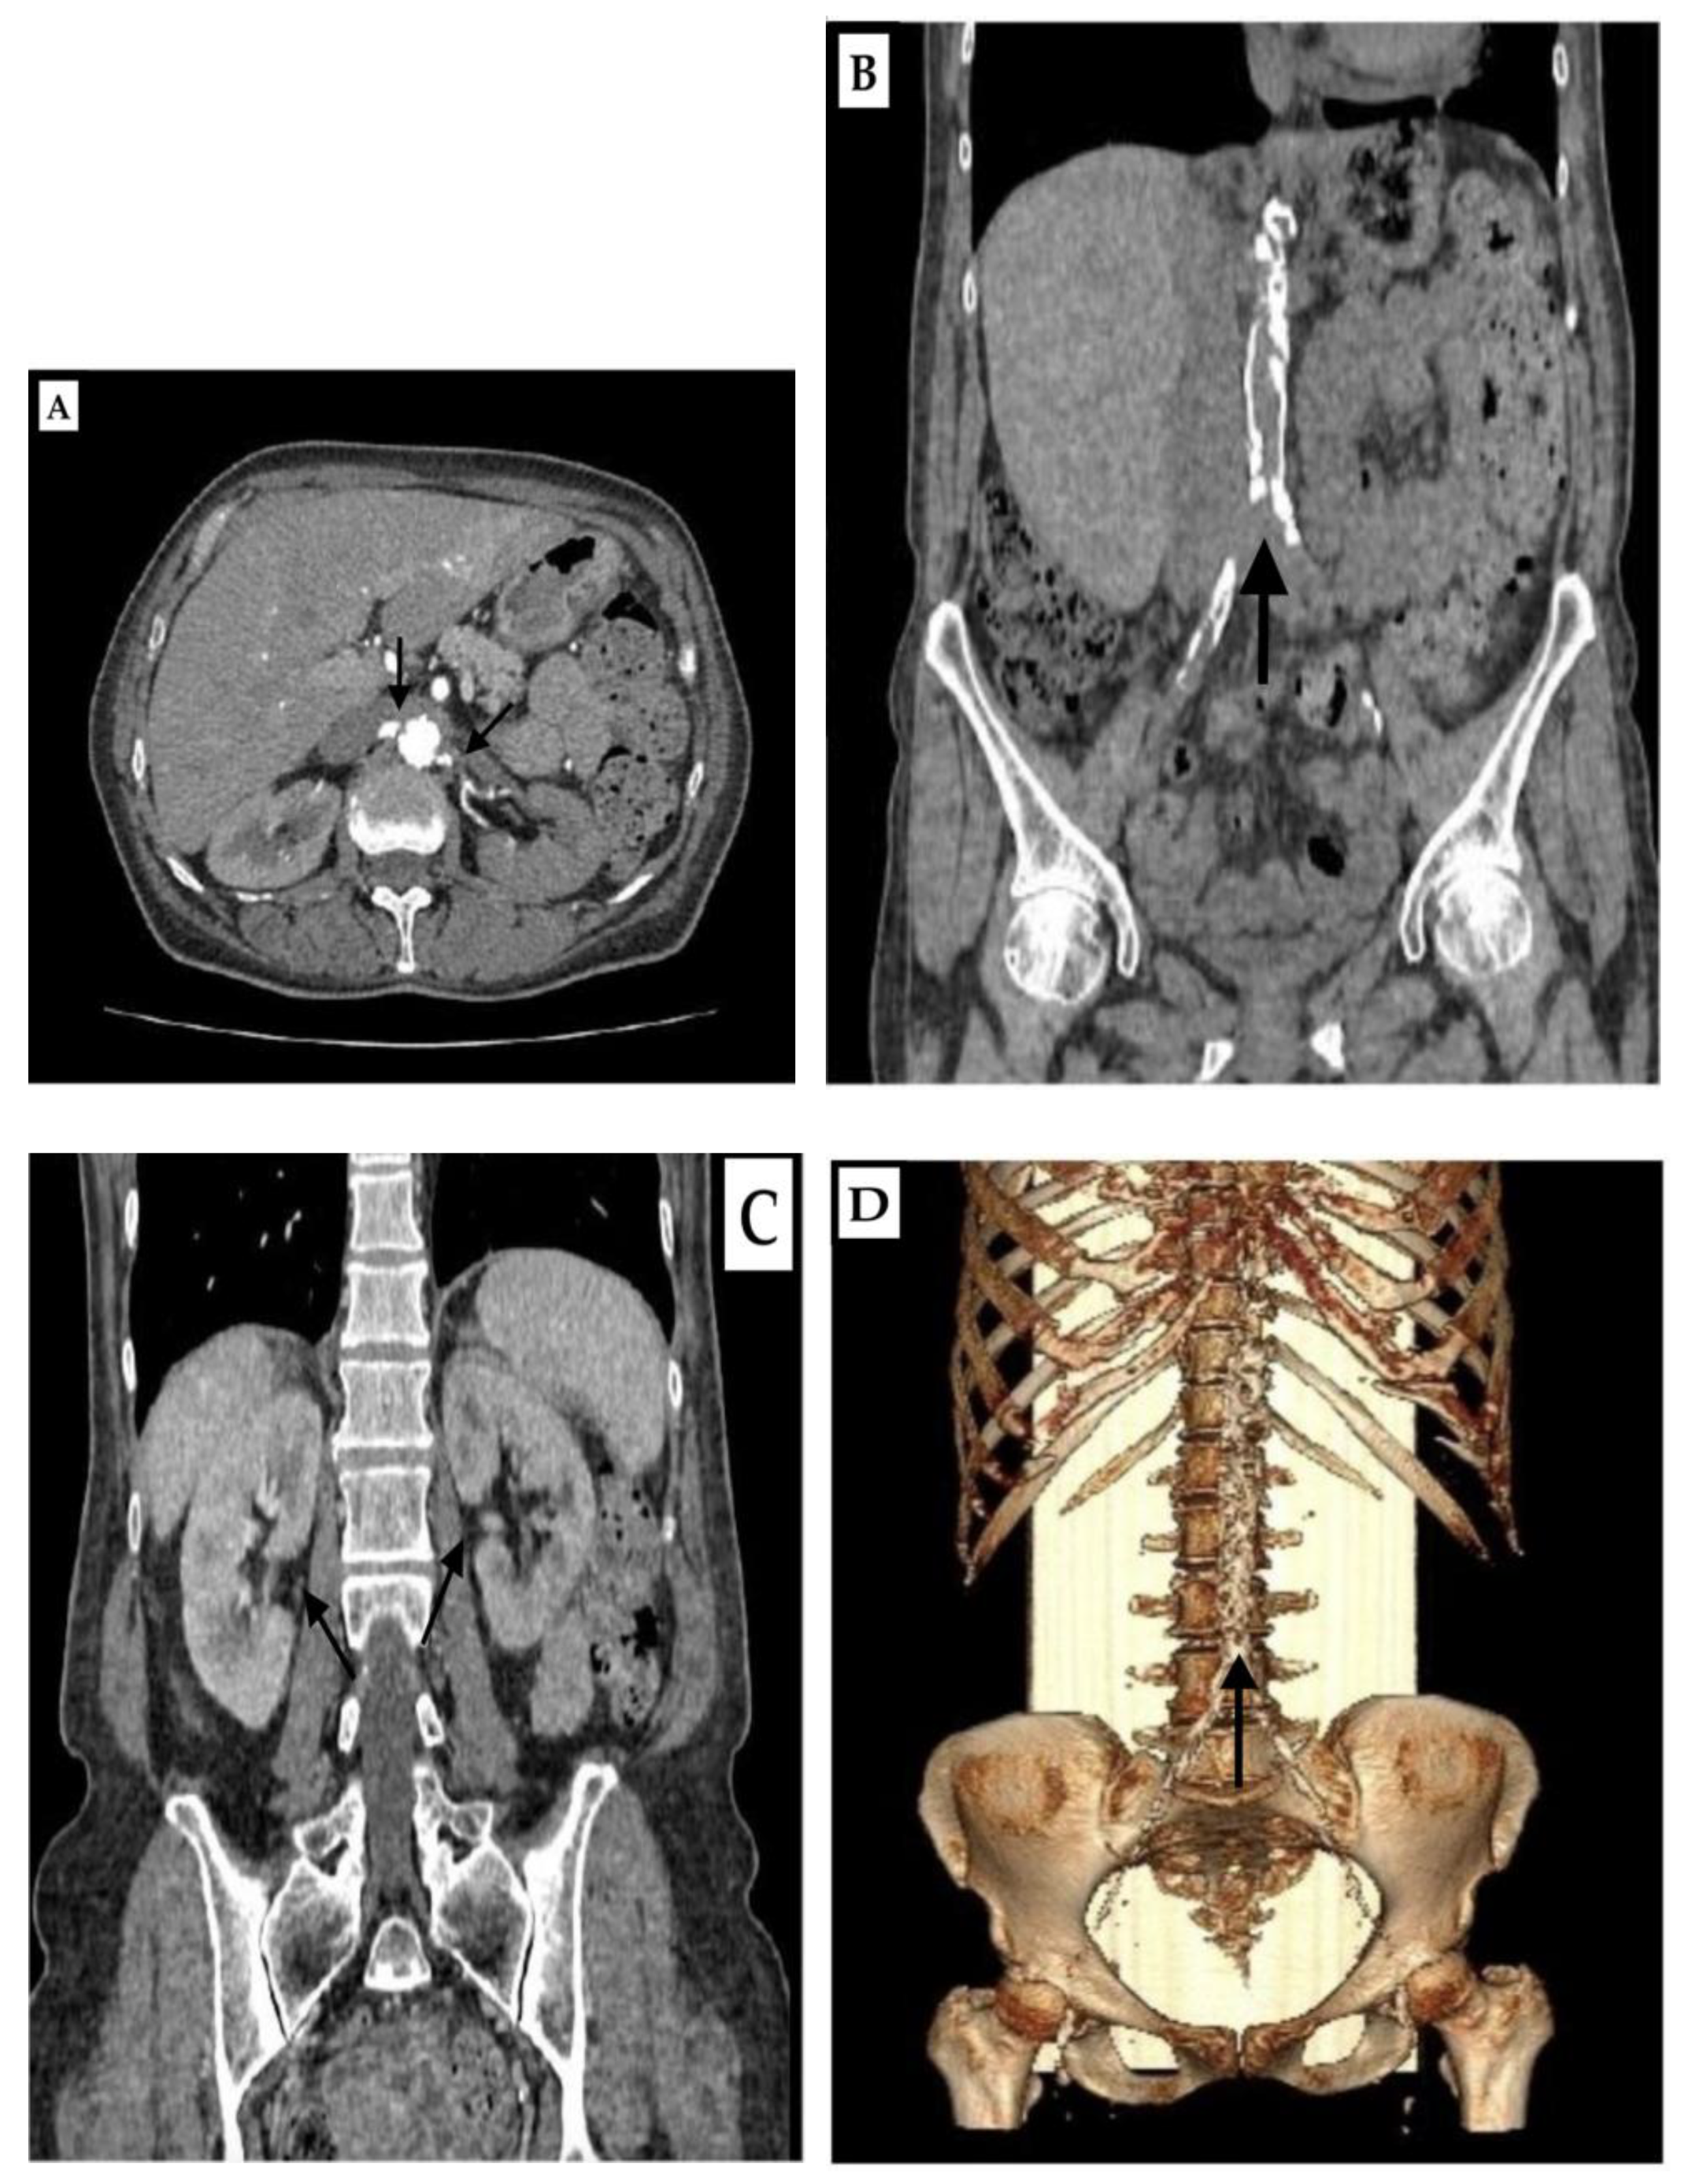

The chest X-ray showed lung emphysema and a 1.3 cm circular shadow in the right perihilar lung field. Computed tomography (CT) pulmoangiography ruled out pulmonary embolism but revealed significant calcification of the thoracic aorta and coronary arteries, centrilobular emphysema with interstitial edema, and pleural effusions with atelectasis of the posterior basal segments. Nelson’s segment of the lower right lobe showed a benign nodular alteration with a diameter of 100 mm, corresponding to a granuloma. The middle lobe had three ground glass nodes with a diameter of 4.7 mm. There were no signs of an active tumor process. Overall, the heart was enlarged. Spirometry suggested mixed ventilatory impairment, predominantly restrictive. Computed tomography angiography (CTA) of the abdomen revealed significant coarse calcifications in the abdominal aorta wall and its branches (Figure 2B), narrowing the lumen to 2 mm at the ostium of both renal arteries (Figure 2A). CT aortorenography confirmed significant right RAS at the ostium and left renal artery occlusion. The committee of vascular surgeons at the institution of the first hospitalization declared that percutaneous transluminal angioplasty (PTA) was impossible due to the high risk of the procedure. Because of the inability to perform PTA, it was determined that renal insufficiency could not be recovered, so we started to prepare the patient for a permanent HD treatment regimen.

Figure 2. (AD) Computed tomography angiography of the abdomen. Axial section, arterial phase, and narrowed lumen at the level of origin of renal arteries (A). Native shot, coronal section, and highly calcified aorta (B). Coronal section, porto-venous phase, and both kidneys post-contrast-opacified (C). Volume rendering (VR) view of a very pronounced calcified aorta (D). (Black arrows).